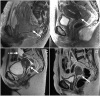

Gynecological malignancies including primary cervical cancers are frequently treated with chemotherapy and radiation. Fistulas affecting the gynecological organs and surrounding cavities are a known consequence of radiotherapy due to focal necrosis of the regional mucosa. In this report, we will demonstrate a rare case of a posterior vaginal wall rupture with resulting fistulization into the peritoneal cavity in a 50-year-old female patient with squamous cell carcinoma of the cervix status postchemoradiotherapy. Magnetic resonance imaging (MRI) showed a discontinuity in the posterior vaginal wall near the fornix with extravasation of ultrasound gel used as contrast into the intraperitoneal compartment. Patient later presented with peritonitis like signs and symptoms and was treated successfully with antibiotics. Vaginal gel should be used with caution in patients with prior history of radiation due to the possibility of vaginal rupture which may lead to peritoneal vaginal fistula and contrast extravasation.